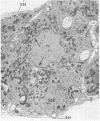

A knowledge of the biological characteristics of carcinogen-induced hyperplastic nodules of rat liver may be important in the understanding of cancer development. Although its biological role remains to be elucidated, the level of microsomal epoxide hydrase (epoxide hydrolase, EC 3.3.2.3) is 5- to 7-fold greater in hyperplastic nodules nodules induced by feeding the hepatocarcinogen 2-acetylaminofluorene than in liver of control rats. After removal of the carcinogen from the diet, the high level of the enzyme is maintained in those nodules that persist and in the hepatocellular carcinomas that subsequently develop. The availability of antibody to the epoxide hydrase made it possible to use electron microscopic immunocytochemistry to localize this enzyme in the cells of hyperplastic nodules. The immunocytochemical procedure provides direct visual evidence for the presence of this enzyme in smooth endoplasmic reticulum and also in rough endoplasmic reticulum (including the nuclear envelope) of the nodule's parenchymal cells.